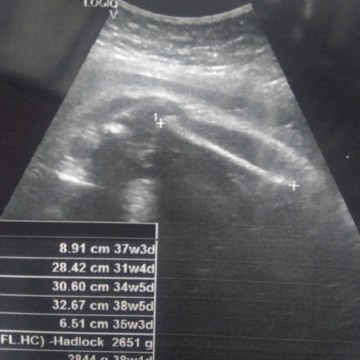

อยากรู้เพศแต่หมอไม่บอก

แม่ๆดูรู้ไม๊คะ แบบนี้หญิหรือชาย

รอลุ้นเพศเลยค่ะ